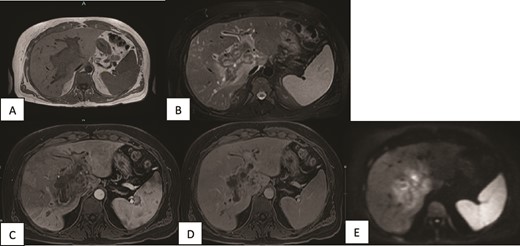

A contrast-enhanced MRI of the liver was done and showed periportal infiltrative soft tissue changes at the hilum of the liver with irregularly enhancing margins on contrast-enhanced T1-weighted images. There was also minimal diffusion restriction on diffusion-weighted images and which was confined to the periportal tracts involving the main portal and intrahepatic right and left periportal spaces. The presence of portal vein thrombosis was also confirmed (Fig. 2).

MRI of the liver (A, B) Axial T1WI and T2WI fat-saturated images revealing an isointense central rim with hypointense periportal edema on T1-weighted images and a hypointense rim along the portal tracts with periportal edema on T2-weighted images. (C, D) Axial T1WI postcontrast images obtained at the arterial and porto-venous phases showing mild peripheral enhancement with non-enhancement of the portal vein. (E) DWI showing minimal diffusion restriction at the hilum.